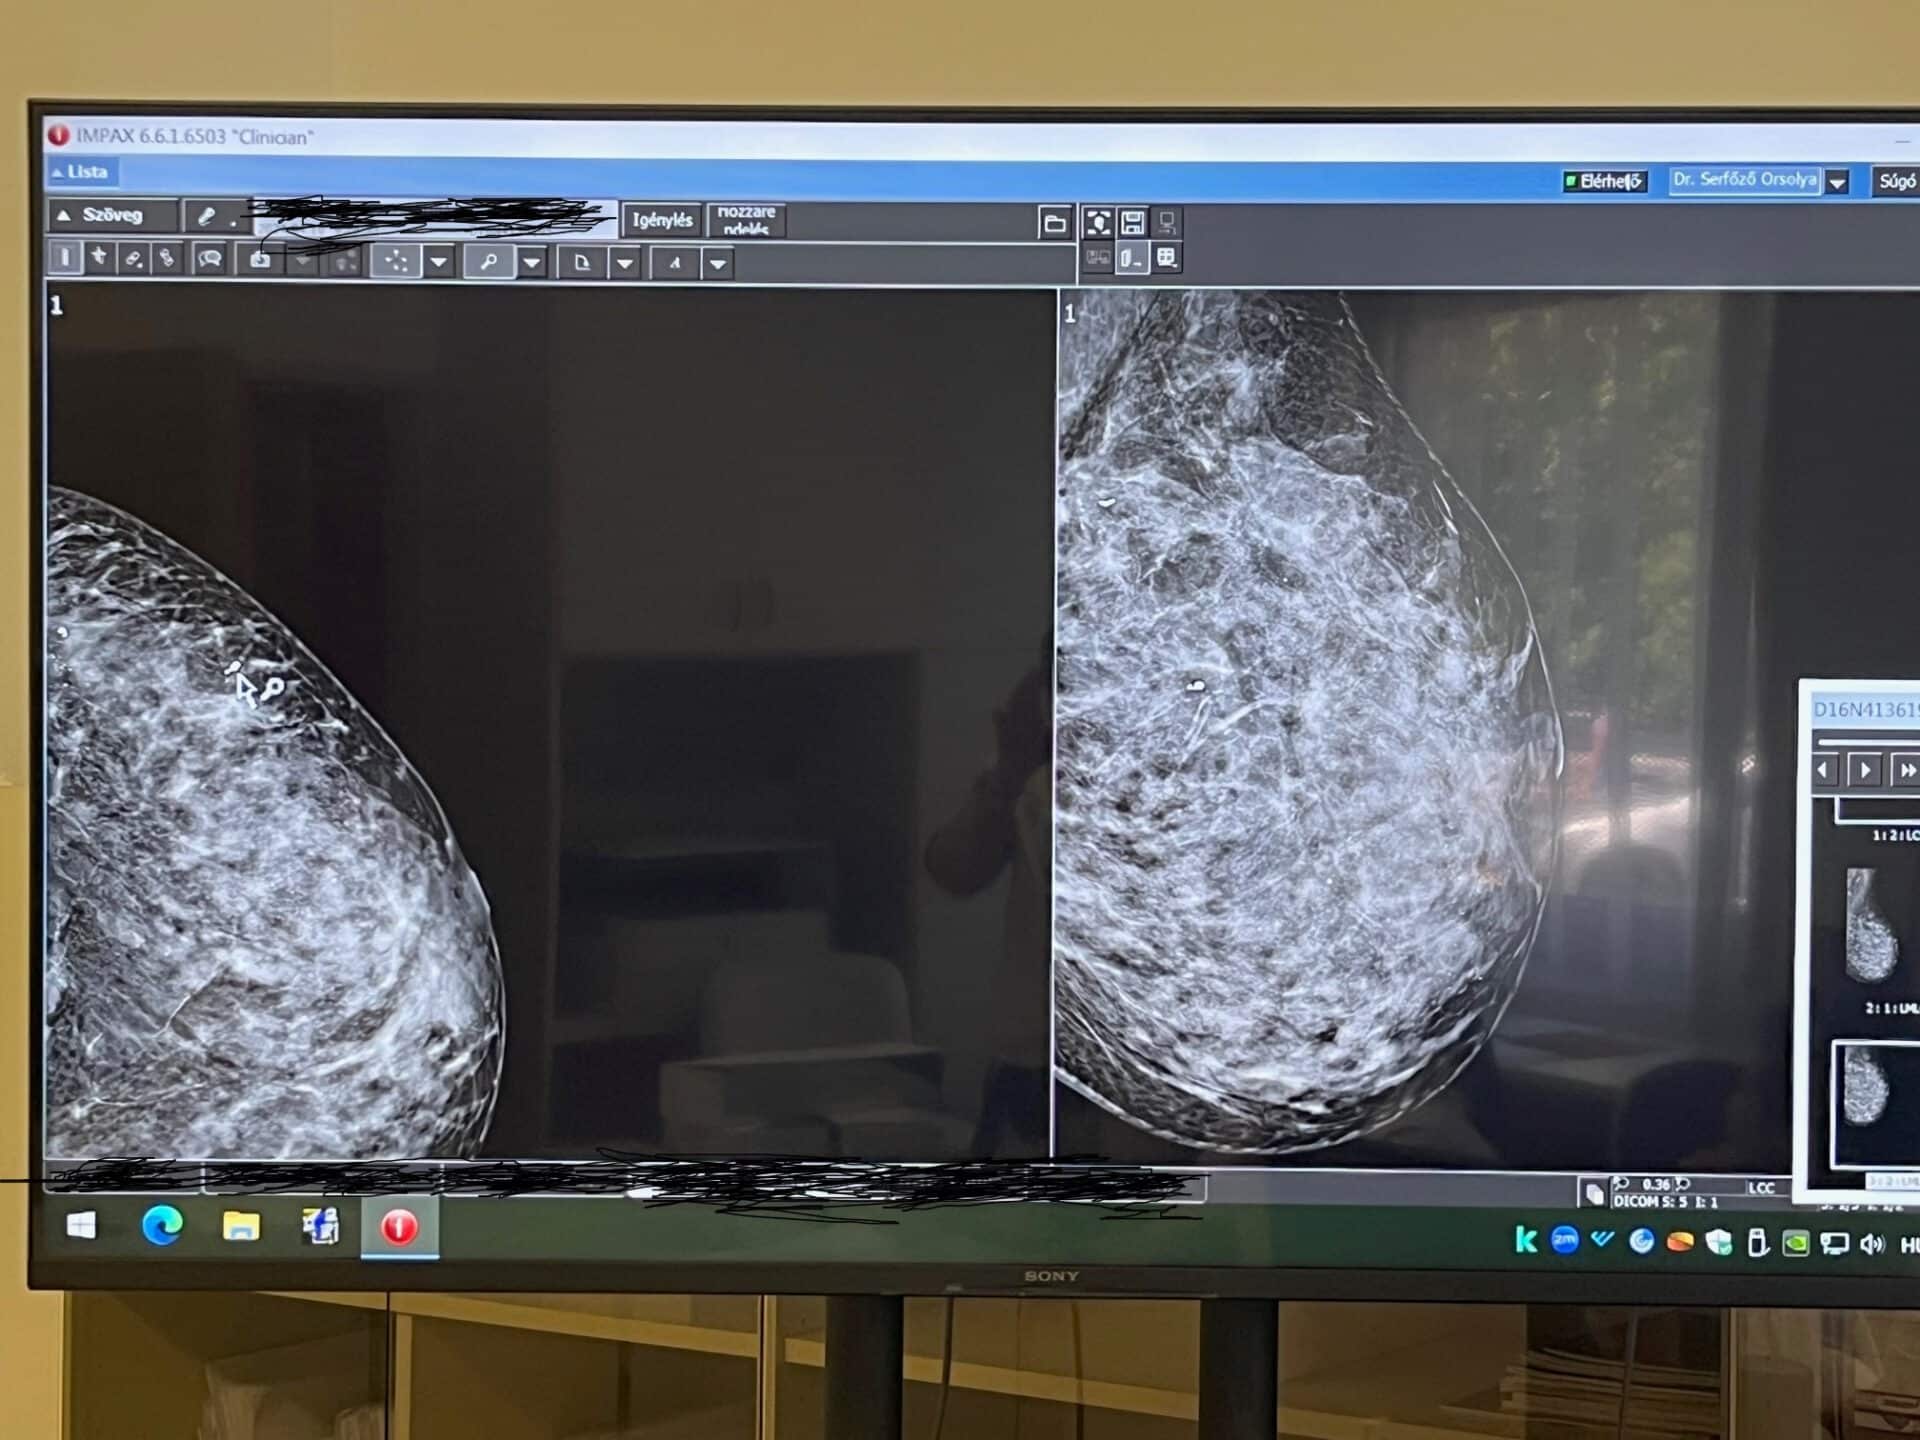

A jelölő klipek segítségével a szakemberek nagy pontossággal tudják meghatározni az érintett területet. Ez különösen fontos azokban az esetekben, amikor a kezelések hatására a daganat nagymértékben összezsugorodik – vagy akár teljesen el is tűnik –, de mikroszkópos szinten még maradhatnak kóros sejtek. Ennek műtét során, és a kivett mintában való megtalálását segítik ezek a jelölők. A Bács-Kiskun Vármegyei Oktatókórház Onkoradiológiai Központja a térség meghatározóbb emlődaganat-ellátó intézménye, ahol a Mamma Klinikával szoros együttműködésben működtetett emlődiagnosztika és mintavétel, valamint az onkológiai és emlősebészeti ellátás összehangoltan, egymásra épülve működik. A jelölő klipek sokkal pontosabbá teszik a korszerű sebészeti tervezést és a patológiai kiértékelést.

A jelölő klip mutatja meg a daganat eredeti helyét, így a sebész és a patológus is pontosan tudja, mely területet kell eltávolítani vagy vizsgálni. Ez a technológia az emlődaganat-kezelés egyik kulcsa. A beavatkozás ultrahang-vezérelten történik, és nagyjából egy biopsziához hasonló kellemetlenséggel jár. A klipek behelyezése a kórházban, a Mamma Klinikán zajlik, ahol a diagnosztika, a mintavétel és a sebészeti előkészítés egységes betegútként, gyorsan és magas szakmai biztonsággal valósul meg.